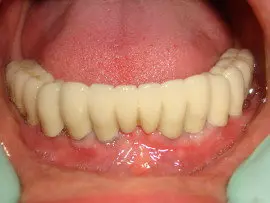

These technology also can be used for designing the CAD CAM prosthesis made on dental implants.

The entire procedure of assessment, treatment planning, selection of implant systems and final prosthesis  planned “virtually” before treatment begins. Patients benefit from being able to visualize, fully, current state of need and final outcome possibilities, based on their choice of restoration components (types of crowns, abutments, shape, color shading, size, etc).